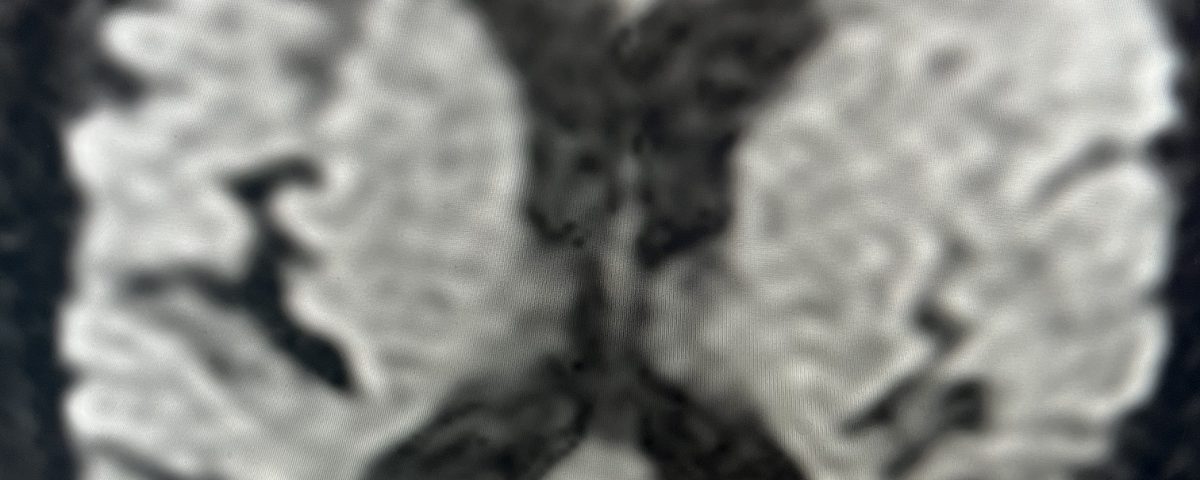

He was studied with noninvasive imaging most significantly, which was a CTA that confirmed a high-grade carotid stenosis from a calcified atherosclerotic plaque. This is seen in Figure 3 which is a coronal CTA. The patient was evaluated for carotid revascularization, and given the high-grade critical stenosis detected on the CTA and the carotid duplex, he was a good candidate, given the high-stroke risk of the lesion if left untreated.

Fig. 3 – Pre-operative CTA image confirms high-grade carotid stenosis from a calcified atherosclerotic plaque.